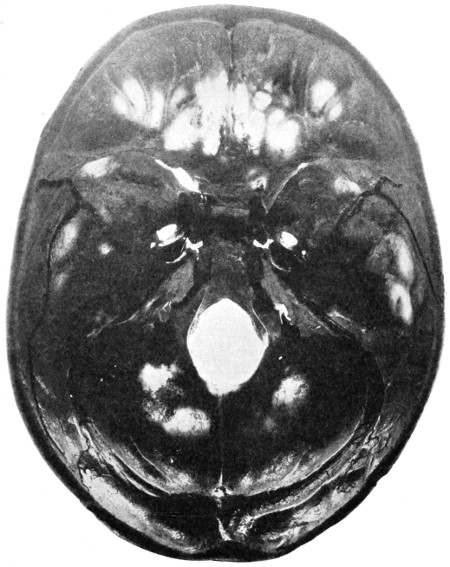

75. A large right-sided temporo-sphenoidal abscess 256

76. To illustrate the pressure effects of a temporo-sphenoidal abscess 257

77. A cerebellar abscess 259